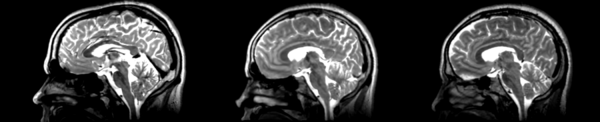

Different subject registration

- 01053-t2 -> 01031-t2 = Result. All the images shown have the moving image on the left, the resultant image in the middle, and the target image on the right.

B-spline

01053>01031_bspline.png = looks good in terms of size. odd warping of frontal/temporal lobe and cerebellum area, but otherwise good coregistration.

Diffeomorphic Demons

01053>01031_demons.png = 10 minutes. Window/leveling initially off. Otherwise, it looks really good. Not much distortion.

Register Images module

Initial

01053>01031_RI_initial.png - looks like the original 01053 image, but shifted, which is expected. resolultion a little worse.

Rigid

01053>01031_RI_rigid.png - center ventricles are mostly aligned, but not perfectly. in axial view, brain is more crooked than in initial scan... especially in frontal lobe.